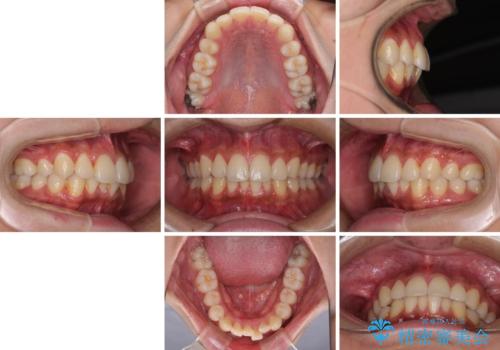

矯正治療の後戻りをインビザライン・ライトで解消

- 矯正治療の後戻りを気にして来院された患者様です。

後戻りは軽微であったので、インビザライン・ライトにより矯正治療を行うこととしました。

インビザライン・ライトは提供されるマウスピースの数に制限があり、通常のタイプよりもマウスピース提供期間が短くなっている一方、安価に治療を行うことができるプランです。

治療のゴールも変更できないため、軽微な歯列不正や、後戻り改善などに適しています。

矯正治療後は、再度後戻りすることを極力回避するために、下顎前歯の舌側を細いワイヤーを用いて保定することとしました。